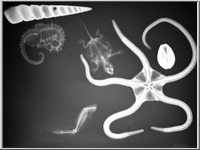

A képekre kattintva a röntgenfelvételek üveglemezeinek reprodukcióit, a kis képek jobb felső sarka melletti ikonokra klikkelve pedig az üveglemezeket védő, Gothard által feliratozott, a felvételek adatait tartalmazó borítékok reprodukcióit láthatjuk.

Az 1. sorszámú lemez elveszett, csak papírmásolat maradt fenn róla. A 25. és 26. sorszámú borítékok 2-2 felvételt tartalmaznak (itt a-val és b-vel jelölve), míg a 32. sorszámú lemez eltört, két darabban van.